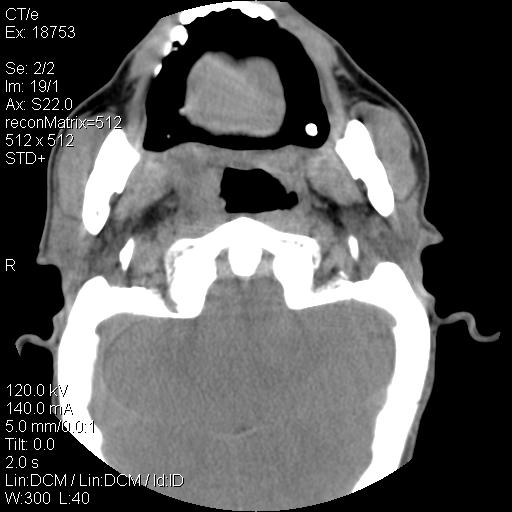

标题: CT21693:男 58岁 右侧咽部疼她2天余 PE:右侧扁桃体肿大 压痛 [打印本页]

标题: CT21693:男 58岁 右侧咽部疼她2天余 PE:右侧扁桃体肿大 压痛

右化脓性扁桃体炎症伴咽后壁脓肿形成.

以下是引用zjzjr在2009-8-19 21:07:00的发言:[br]右化脓性扁桃体炎症伴咽后壁脓肿形成.